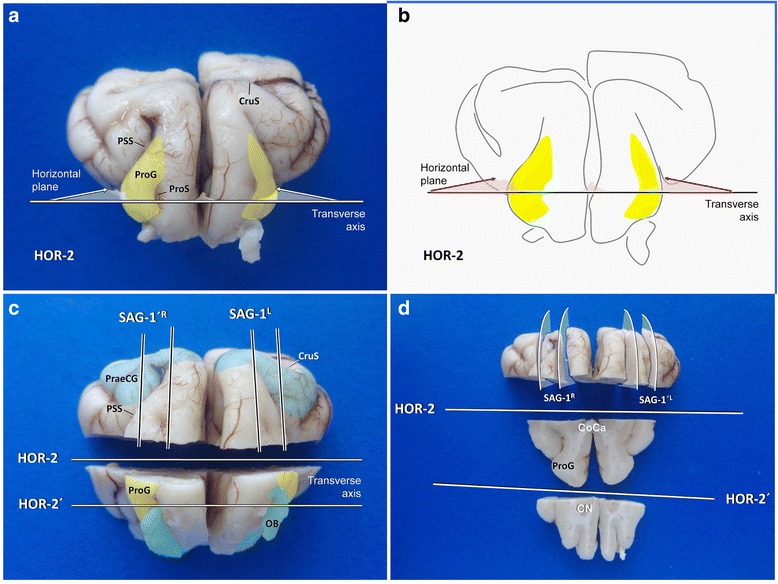

It proves useful to approach the olfactory bulb and cortex, its connections to the periventricular brain and subventricular zones using horizontal sections. To conduct the first horizontal section (HOR-2), the blade is inserted in laterolateral axis at the proreus gyrus and the tissue is cut in rostrocaudal direction (Fig. 13). With the previous transverse cut, set caudal to the genu of the corpus callosum, both hemispheric parts stay connected, which facilitates cutting and processing. Depending on the brain size, one or two further horizontal sections (HOR-2′, −2″) are performed at 3–4 mm interslice distances ventral to HOR-2 (Fig. 13).

Fig. 13.

Planning and performance of fronto-olfactory dissection in a dog; rostral view. CN: caudate nucleus; CoCa: corpus callosum. CruS: cruciate sulcus; OB: olfactory bulb; PraeCG: praecruciate gyrus; ProG: proreus gyrus; ProS: prorean sulcus PSS: presylvian sulcus

Having achieved this, two sagittal sections through the lateral third of the proreus gyrus (SAG-1Left/Right) and again about 3 mm lateral to these (SAG-1′L/R) allow for inspection of and sampling of motor cortex, flanking the cruciate sulcus rostrally (pre-cruciate) and caudally (post-cruciate) (Fig. 13). Further sagittal sections in vertical plane (SAG-1″ L/R) may be taken if for diagnostic purposes.

An example of the tissue slabs achieved by trimming of tissue block B is provided in Fig. 14.

Fig. 14.

Overview of main brain slabs of Block B in correct angle of section. A selection of these may be further processed for histology. Asterisks mark our recommendation for systematic epilepsy pathology studies